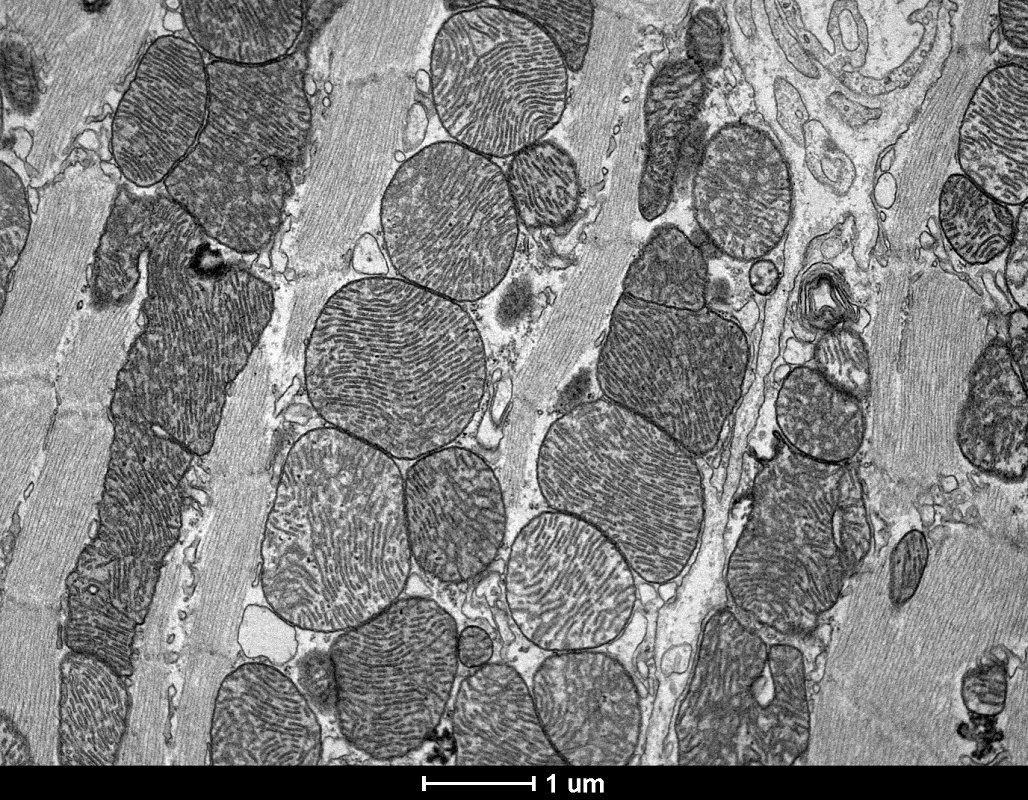

Cardiomiócito (célula muscular cardíaca) de camundongo, onde são observados perfis de sarcômero (unidades contráteis) e numerosas mitocôndrias.

Equipamento: Microscópio Eletrônico de Transmissão Tecnai G2-12 – Spirit Biotwin FEI – 120kV

Imagem cedida por Hermann Alecsandro Rodrigues, Marina Cruz e Cristina Guatimosim Fonseca, Departamento de Morfologia, ICB, UFMG.